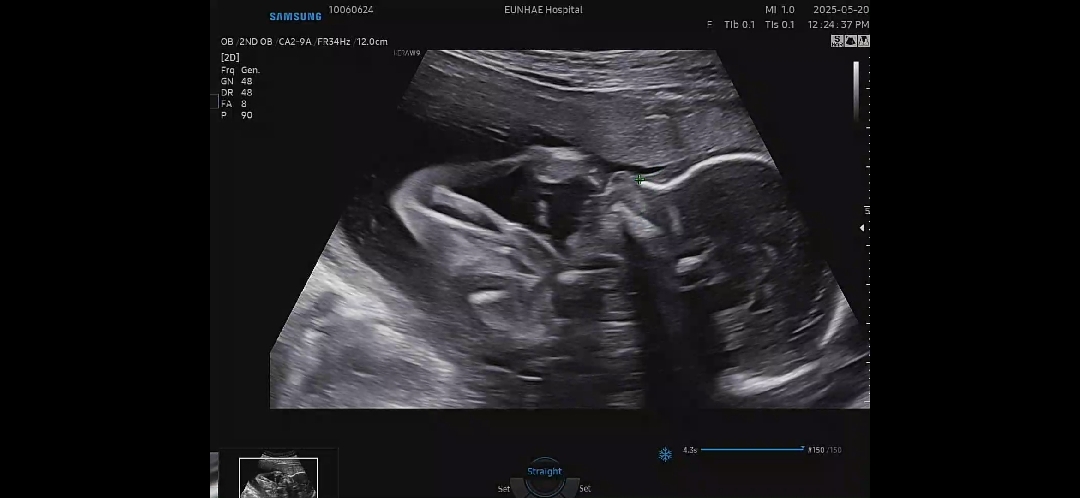

저는 26주0일에 딱 임당+입초 했어요. 입초 예뿌게 나왔어요ㅎㅎ 저희 병원은 한번에 안보일 경우 담주나 다담주 한번더 보기 때문에 26주에 보더라구요. 28주까지가 잘보인다고..

저두26주4일에 입초해용 병원마다 달라서 문의해보시는게 좋을거같아요

저희병원은 입초 필수 아니라고 얘기 안하면 안봐주더라고요! 더 늦기전에 먼저 함 물어보셔용 그나저나 아기 이마도 볼록 콧대 아주 선명하니 이쁘네요~~^^